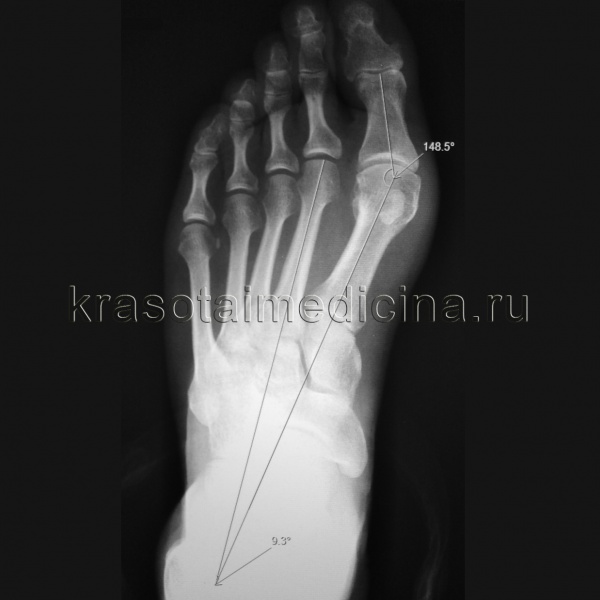

Степень выраженности патологии определяют с учетом двух величин: угла между II и I плюсневыми костями (Intermetatarsal angle) и угла, под которым I палец отклонен по отношению к I плюсневой кости (Hallux valgus angle). Степени Hallux valgus:

- 1 степень – угол между плюсневыми костями менее 12 градусов, угол отклонения I пальца менее 25 градусов.

- 2 степень – величина угла колеблется от 12 до 18 градусов, I палец отклоняется более чем на 25 градусов.

- 3 степень – угол между костями плюсны составляет более 18 градусов, угол отклонения первого пальца достигает более 35 градусов.

- Рентгенография стопы. Является основным диагностическим методом при Hallux valgus. Рентгенолог производит специальные измерения, на основании которых определяет степень патологии. Наряду со степенью деформации при изучении рентгеновских снимков оценивают выраженность артрозных изменений. О наличии артроза свидетельствует сужение суставной щели, деформация суставной площадки, краевые разрастания и остеосклероз субхондральной зоны.

Рентгенография стопы. Вальгусная девиация первого пальца стопы, с увеличением угла отклонения 1-го пальца и угла между осями 1-й и 2-й плюсневых костей.